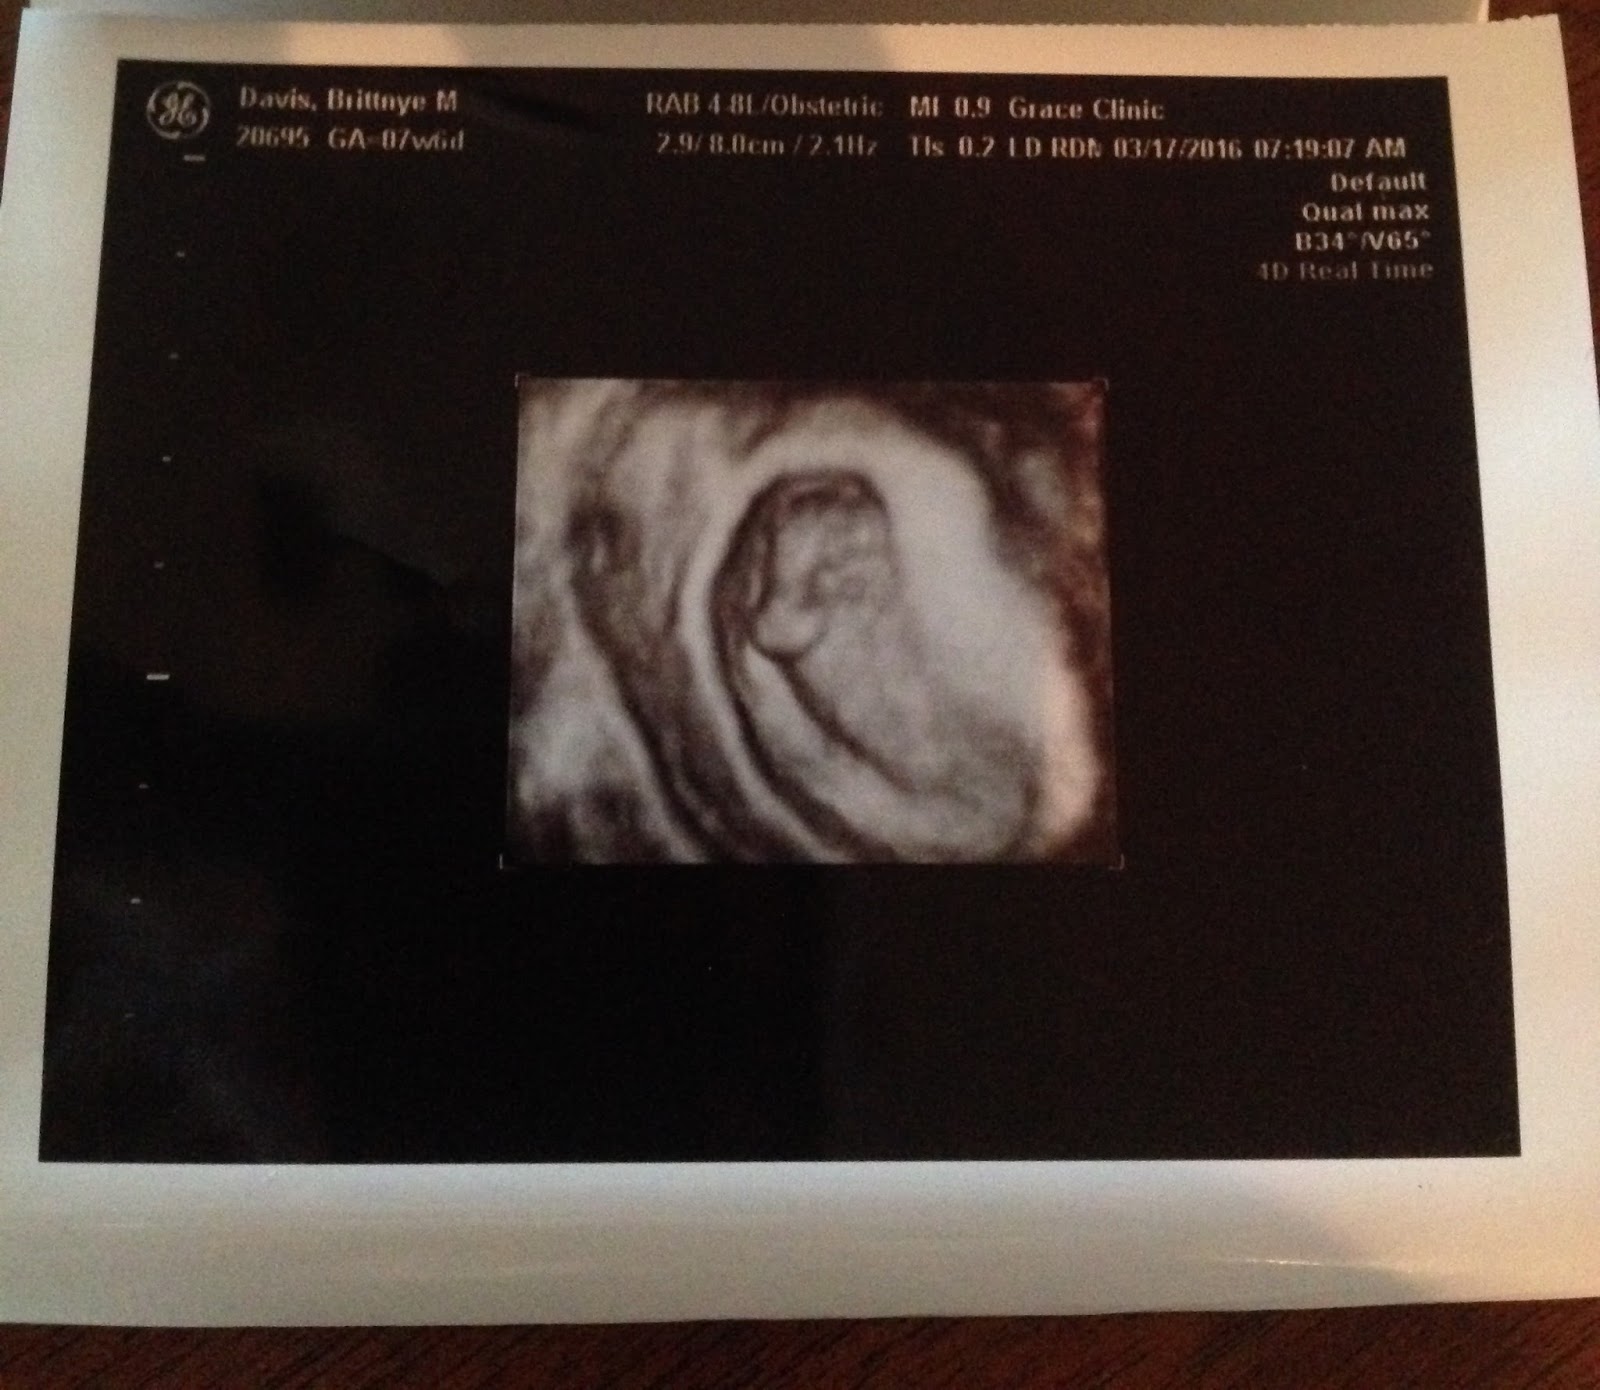

We saw Sugar Bug (as my mom has affectionately dubbed the baby) on Thursday morning for the first time. What an incredible sight! What confirmation, too. I haven't really felt pregnant at all, so it was reassuring to see that there really was someone in there! Aaron and I both starred at the screen, dumbfounded. It was surreal. We saw a little heartbeat. We saw a little shrimp looking baby that was already showing the signs of a tiny arm and head. And we learned that Sugar Bug is due the day after Aaron's birthday, so I've already got a head start on my birthday shopping for him this year.